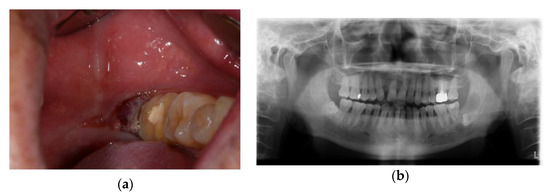

2.1. Case 1: SCC on Right Mandibular Buccal Mucosa

2.3. Case 3: Verrucous Carcinoma on Right Upper Gingiva